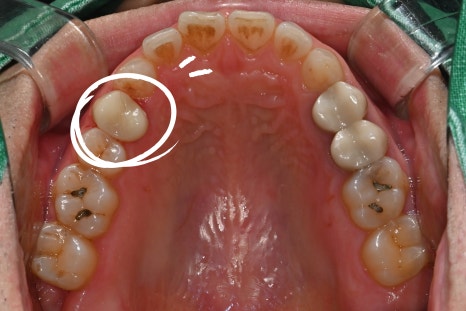

환자분 처음 내원당시

어금니가 꺠지면서 씹을 때 찌릿하고 쑤시는 느낌이 나요

치과에서 찍은 사진과 엑스레이를 확인해보니,

깨진 틈으로 세균이 들어가

신경이 이미 많이 손상된 상태였습니다.